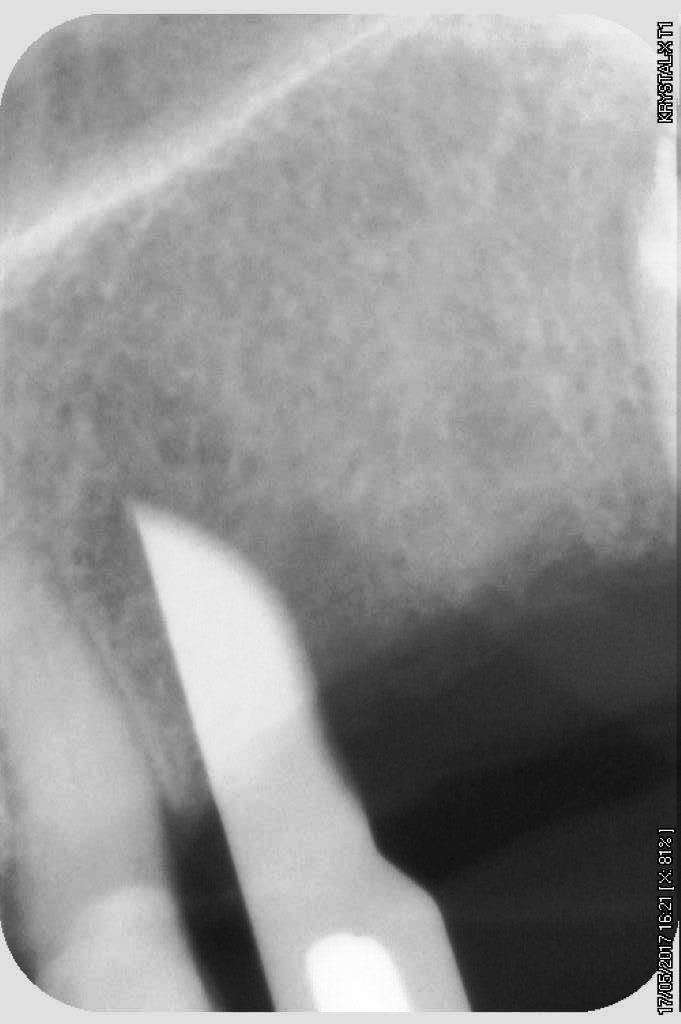

petit cas sympa ancien bridge très mobile....plutôt que d'extraire 25, j'ai déposé la couronne, retraité la dent stabilisation pendant deux mois puis séance d'ostéotension et ce jour pose de deux axioms PX 34120 après expansion...

non, uniquement travail par voie crestale, très légère fêlure niveau 23, mais sans conséquence

comme je n'ai pas fait de décharges osseuse en vestibulaire, j'ai effectivement travaillé toute la longueur de la crête, mais, là j'ai ôtè les expanseurs avant de visser les implants car ce sont des PX qui ont un apex assez fin, pour des regular j'aurais pratiqué différemment.

par contre je suis passé par le stade implants lisse (34100 et 34120)